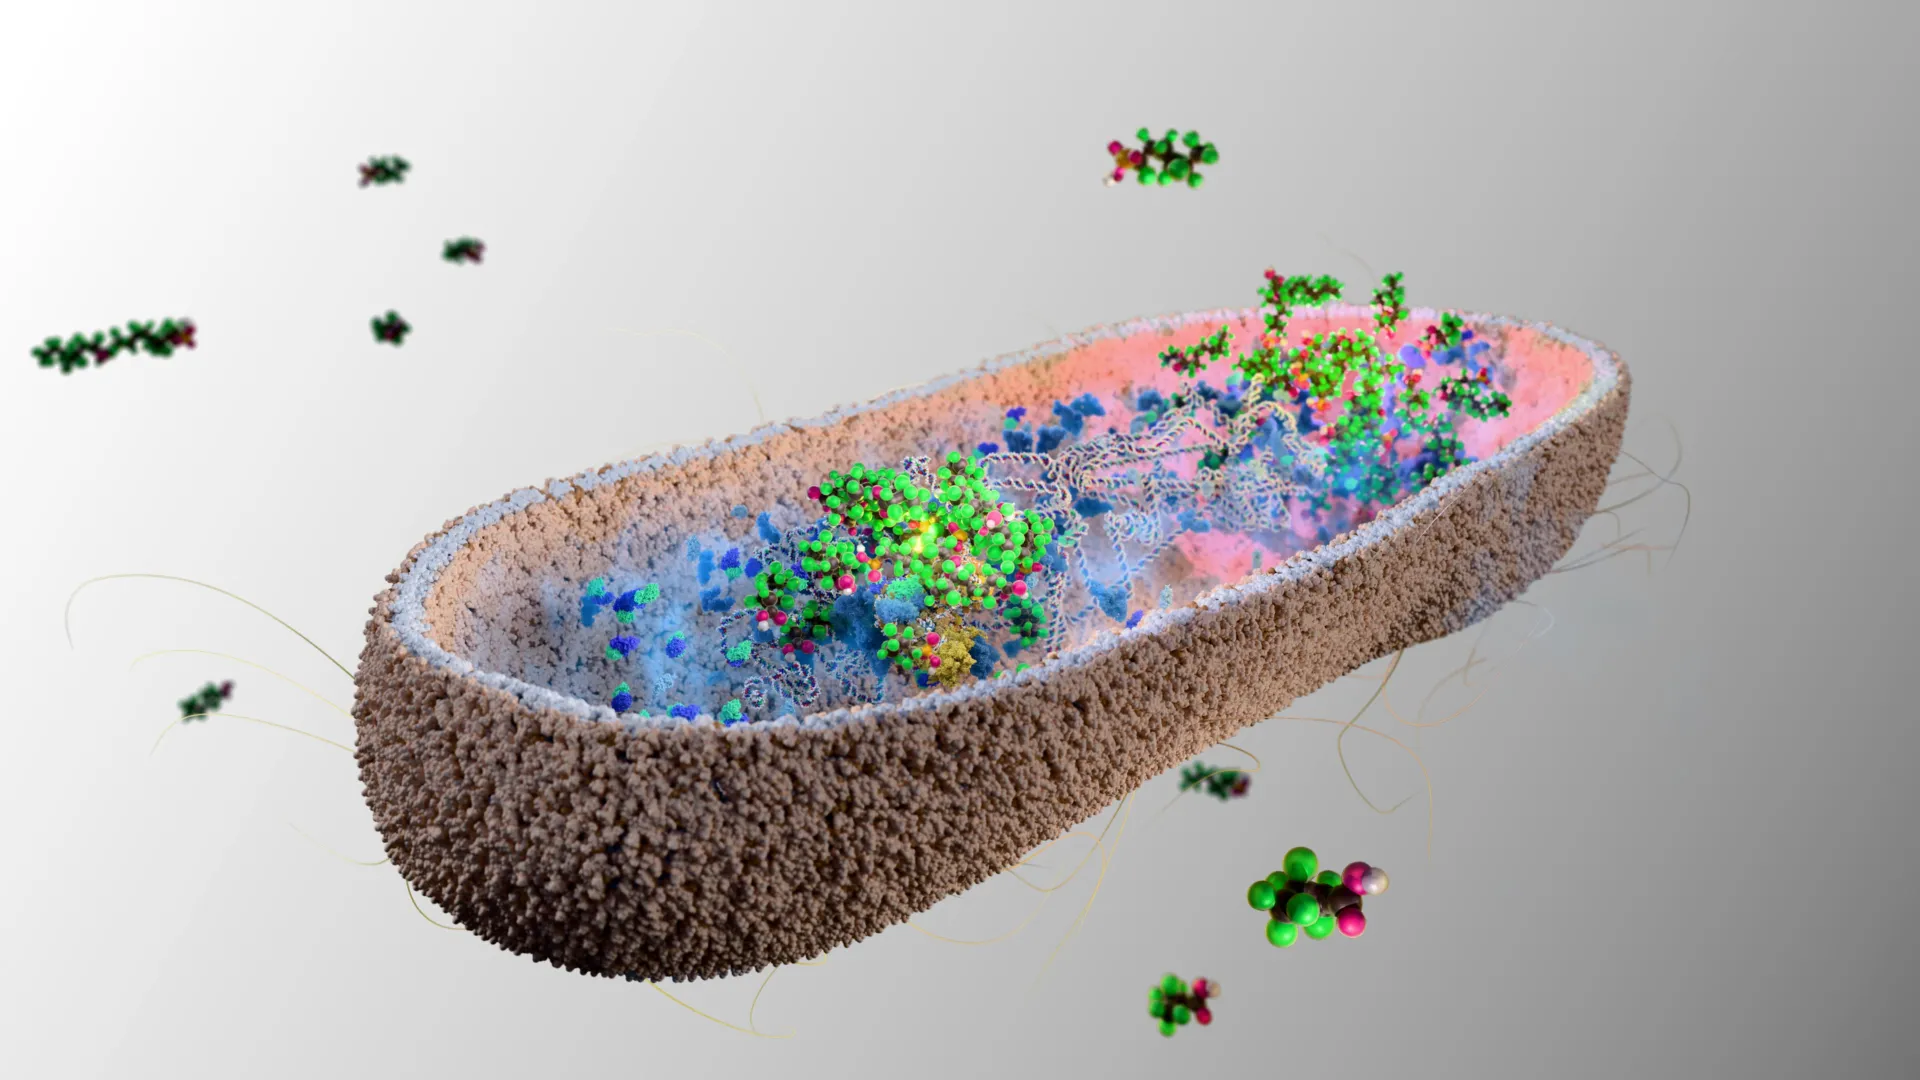

The fatal mutation that lets cancer outsmart the human immune system

New research from UC Davis Comprehensive Cancer Center has uncovered an evolutionary change that may explain why certain immune cells in humans are less effective at fighting solid tumors compared to non-human primates. This insight could lead to more powerful cancer treatments. The study was published in Nature Communications. It…